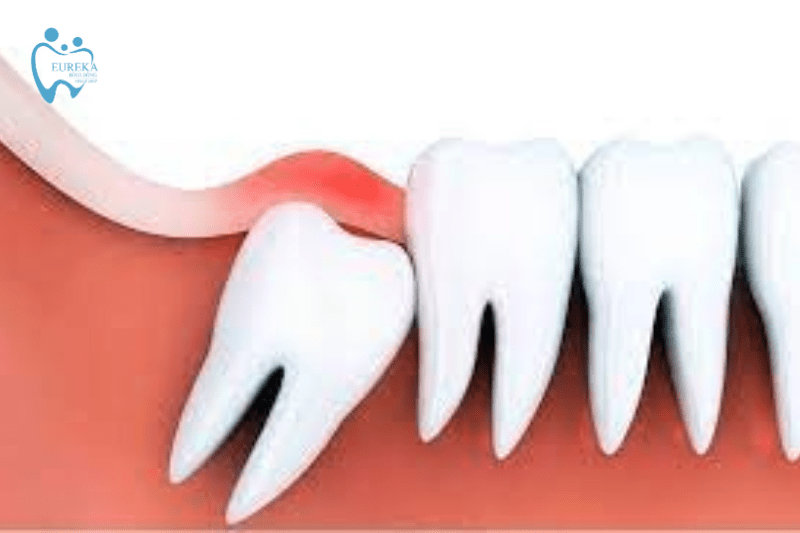

- Viêm lợi do vị trí mọc răng khôn

Răng khôn mọc ở vị trí trong cùng của hàm nên không có đủ vị trí để nhô hẳn mặt răng lên trên hàm được. Vì vậy chiếc răng này không thể mọc tách khỏi nướu mà chỉ mấp mé bờ nướu, nên răng khôn không thể nhô lên hoàn toàn giống những chiếc răng khác. Ở trường hợp này răng cọ sát với nướu trong quá trình ăn nhai và vệ sinh răng miệng từ đó dẫn đến tình trạng lợi trùm răng khôn.